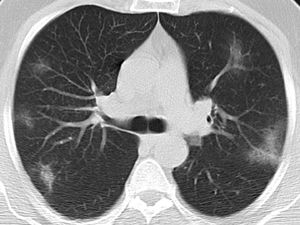

Typical classification (Fig. 2) as a positive test for COVID-19 pneumonia, with an estimated sensitivity of 52.2% (95% CI 47.9%–52.4%), a specificity of 98.5% (95% CI 98.1%–98.4%), an AUC of 0.781 (95% CI 0.731–0.785), a positive predictive value (PPV) of 97.3% (95% CI 94.2%–99.4%), and a negative predictive value (NPV) of 67.9% (95% CI 63.1%–72.0%).